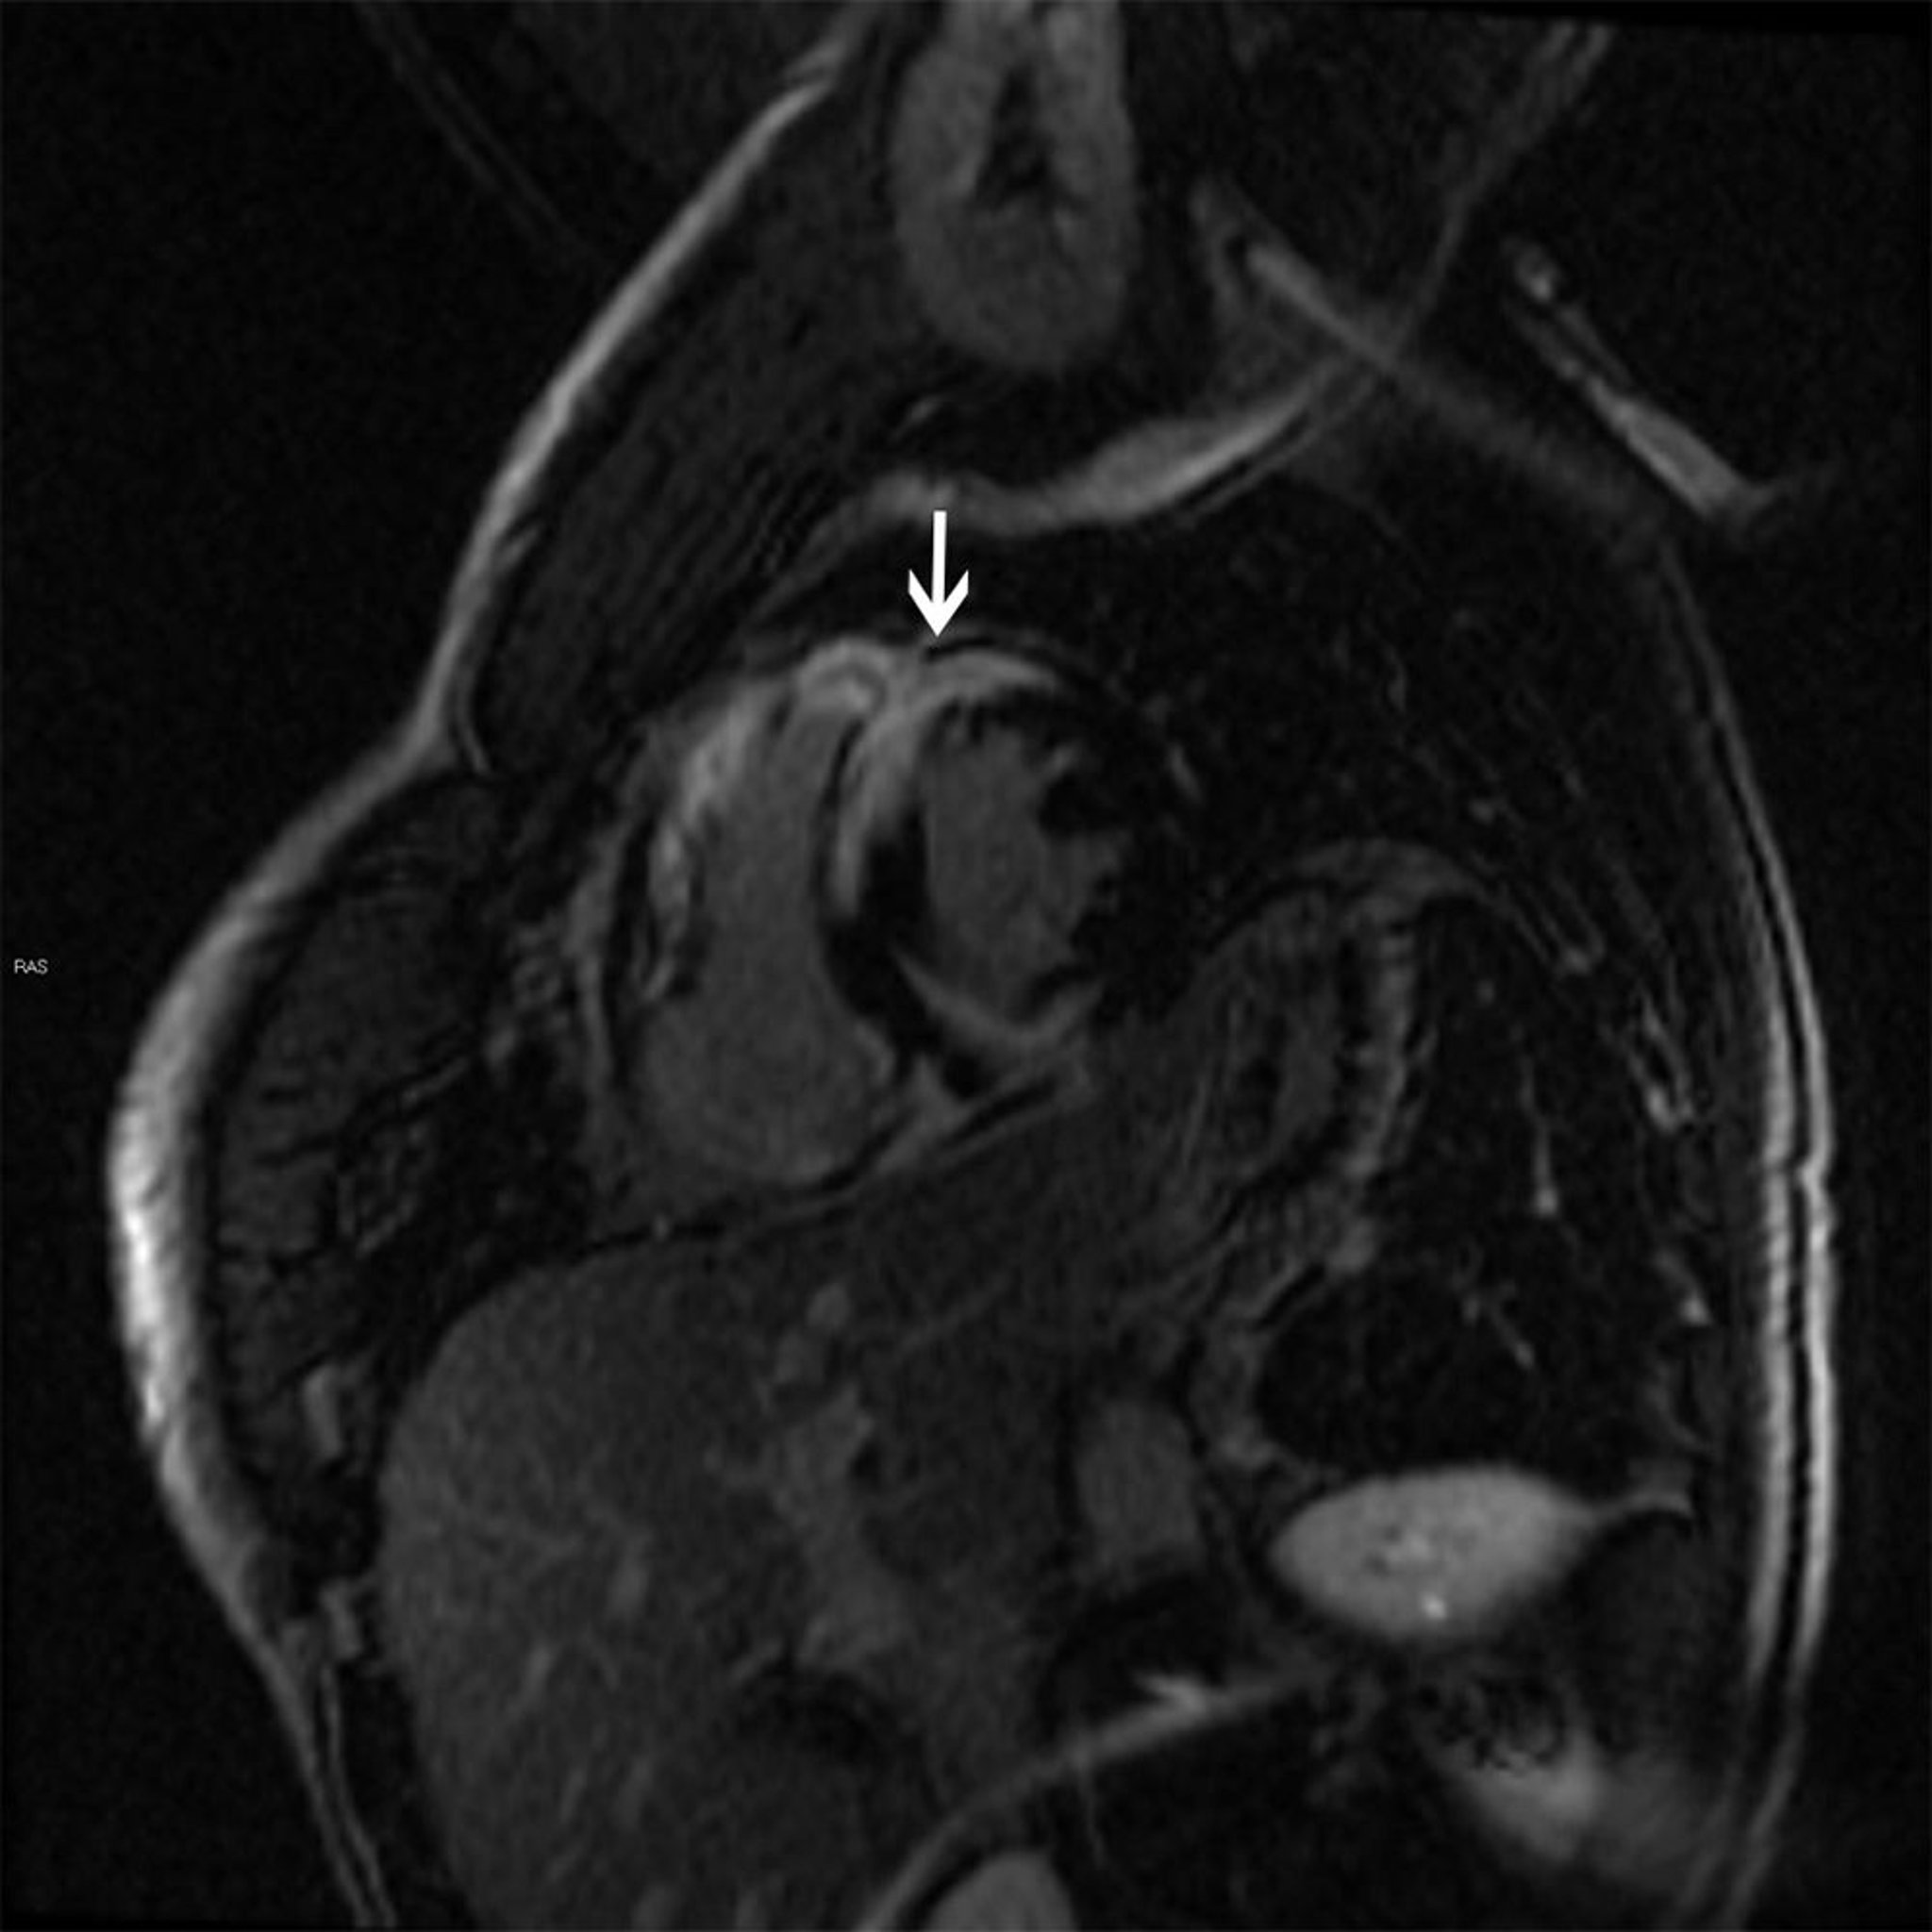

Reperti RM di sarcoidosi cardiaca

Questa RM cardiaca mostra un pattern di enhancement transmurale (freccia) del gadolinio tardivo caratteristico della sarcoidosi, che può causare una cardiomiopatia dilatativa o ipertrofica.